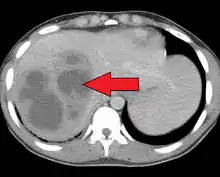

| Liver abscess on axial CT image: a hypodense lesion in the liver with peripherally enhancement. | |